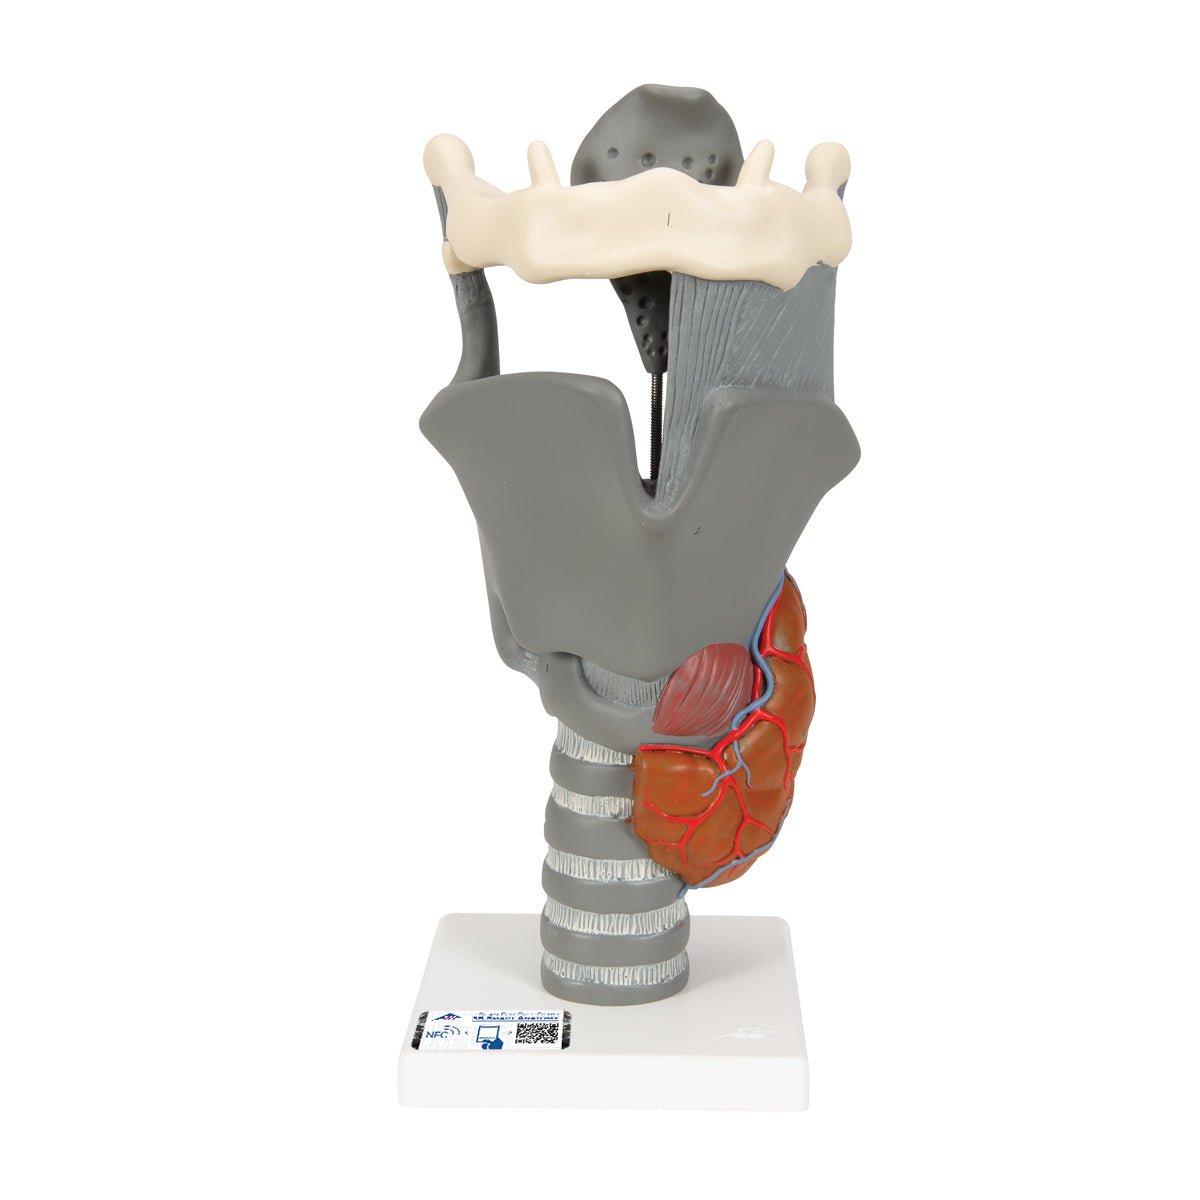

Anatomical models

Selling anatomical models is the mainstay of eAnatomi, although we also spend a lot of resources developing our own anatomical materials such as posters. Anatomical models are used for various purposes and can show both defined tissues, organs and organ systems. Are you looking for a simple model of bone tissue or perhaps an advanced torso model based on MRI technology, you can find it all at eanatomi.com.